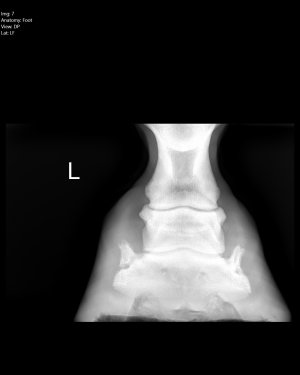

Personally I’d (at least short term) get shoes on him to help address quite clear balance issues. For a variety of reasons, more immediate comfort to assist with better movement (weight loss benefits). Reduce the risk of poor compensatory patterns (potential for soft tissue/arthritic changes).

One alignment is better and you have any weight/metabolic issues under control, by all means aim to remove the shoes.

I’m inclined to agree with ihw re putting shoes on in the short term to correct the imbalances, plus repeat x rays to monitor progress. That is what I did with my homebred with poor front foot balance. The shoes came off again later.

I have to say that I’d not be minded to stay with a farrier who had allowed those imbalances to creep in.